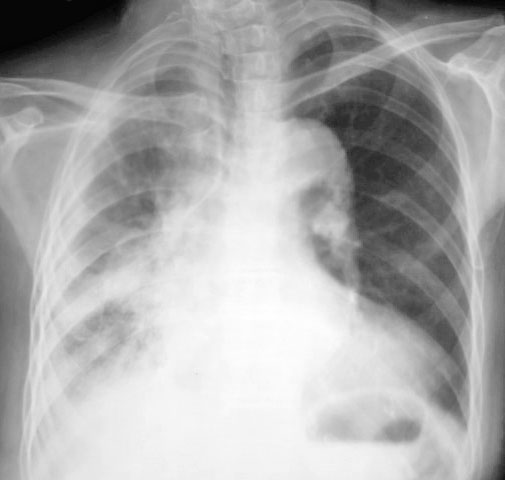

以下是引用马铃薯在2010-6-3 20:49:00的发言:[br]右侧肺门旁见1卵圆形团块样影,肺门结构不清,考虑右肺门旁肿块。右下肺感染。建议ct检查明确一下。[br]右侧胸膜炎。不排除胸膜转移。[br]心影增大。

以下是引用影像之剑在2010-6-3 22:56:00的发言:[br]右侧胸廓塌陷,胸膜增厚。右侧肺野透光度减低,右肺门影增大,似可见模糊块影。右膈面不清,右肋膈角消失。左肺透光度增高,肺内未见明显实质性病变。心影主动脉弓部突出,肺动脉段凹陷,左心缘向左下扩大。左膈清。[br][br]考虑右侧胸膜增厚,胸腔积液,右肺膨胀不全。右肺门模糊块影,建议ct。左肺代偿性气肿。主动脉型心。

以下是引用吴医师在2010-6-3 23:59:00的发言:[br]请与老片对比。如大致相同,考虑胸膜肥厚。如有明显不同,请ct检查。